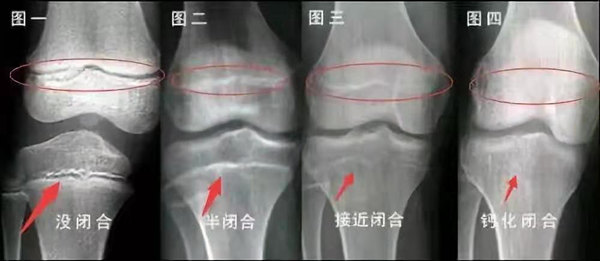

我們都知道,人體的高矮是由骨骼的生長(zhǎng)發(fā)育決定的,特別是下肢長(zhǎng)骨。長(zhǎng)骨呈長(zhǎng)管狀,在長(zhǎng)骨的兩端有一種專管骨骼生長(zhǎng)的骺軟骨,它與干骺端之間有一盤狀軟骨結(jié)構(gòu)稱為骺板(線),在幼兒的X光片上表現(xiàn)為一條較寬的透光帶。 (見(jiàn)下圖)

未成年時(shí)隨著年齡的增加骺軟骨端不斷骨化,骨骼就不斷增長(zhǎng)。當(dāng)骨骺線完全閉合時(shí)骨骼就停止生長(zhǎng),個(gè)子也就不再增長(zhǎng)了。一般骨骺端完全閉合的年齡是18~20歲左右。